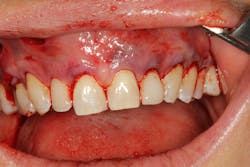

Gingival recession, more commonly described as the condition where the gum tissue surrounding the teeth pulls back, leading to root exposure, is a common periodontal concern (figure 1). Addressing this issue is not only crucial for maintaining oral health but also for achieving cosmetic satisfaction, particularly in individuals dealing with multiple teeth affected by recession (MAR).

PST, developed as a minimally invasive procedure, is designed to reposition gingival tissue to cover exposed roots.1,2 Unlike conventional methods, PST eliminates the need for grafting with tissue from the palate and invasive incisions, significantly reducing postoperative discomfort and scarring (figure 2).